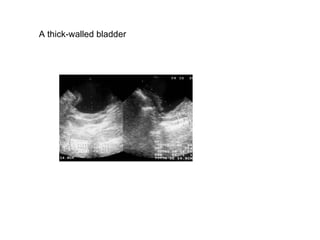

A thick-walled bladder

Schizosomiasis.The typical bladder wall thickening  is shown in this patient who presented with renal failure  and bilateral hydronephros is caused by ureteric strictures

Tuberculosis. The bladder is thick walled and of  small volume.  The patient felt that the bladder was  full at the time of this scan